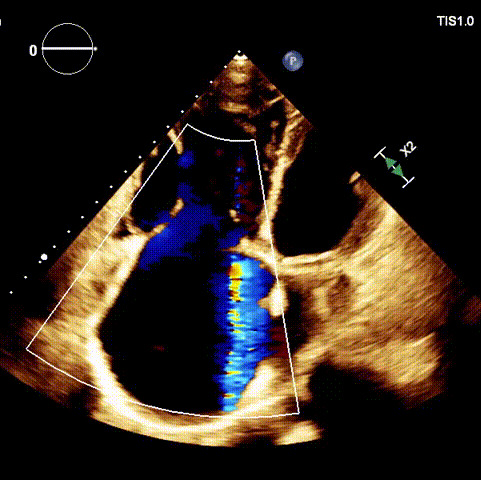

1.二尖瓣位機械瓣位置及功能未見異常;2.雙房及右室明顯擴大(左房收縮容積115ml,右房收縮容積370ml,右室中段左右徑65mm,右室FAC37%),下腔靜脈及冠狀靜脈竇擴張(下腔靜脈直徑44mm,冠狀靜脈竇直徑22mm);3.極重度三尖瓣反流(FTR 6+)。

術前超聲